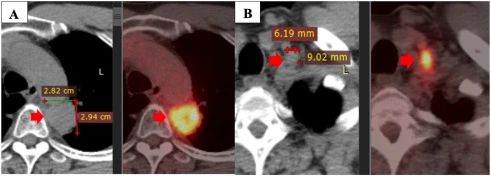

盡管如此,該疾病在 2020 年 5 月繼續發展。PET/CT 掃描顯示原發性腫瘤大小為 28×29 mm,最大標準化攝取值(SUVmax)為 11.2,粘附在縱隔胸膜和主動脈上。此外,左側鎖骨上淋巴結的大小為 9×6 mm,左側門靜脈的一些小淋巴結大小小于 10 mm。

注:一線治療一年后疾病進展:原發性腫瘤(A),左鎖骨上淋巴結(B)。